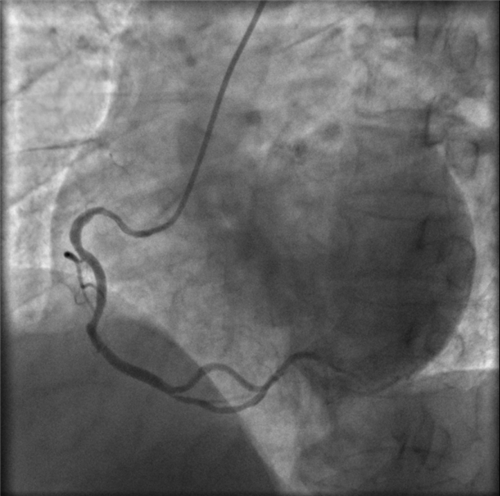

左主干完全閉塞

小心操作導(dǎo)絲及導(dǎo)管,艱難到達(dá)主動(dòng)脈根部,但導(dǎo)管難以“到位”左冠口,“冒煙”見(jiàn)左主干居然完全閉塞了。

右冠近段嚴(yán)重狹窄,未見(jiàn)右向左的側(cè)枝循環(huán)

再行右冠造影,右冠近段也嚴(yán)重狹窄,未見(jiàn)右冠向左冠的側(cè)枝循環(huán)。

在場(chǎng)的醫(yī)護(hù)人員都大吃一驚,原來(lái)他們遇到了離死亡最近的血管堵塞——左主干急性閉塞。由于左冠狀動(dòng)脈主干的血管支配了整個(gè)左心系統(tǒng),一旦血流被急性阻斷,整個(gè)心臟就會(huì)失去2/3的血液供應(yīng)。因此,左主干急性閉塞起病急,進(jìn)展快,死亡率極高,是一種非常高危的胸痛疾病。